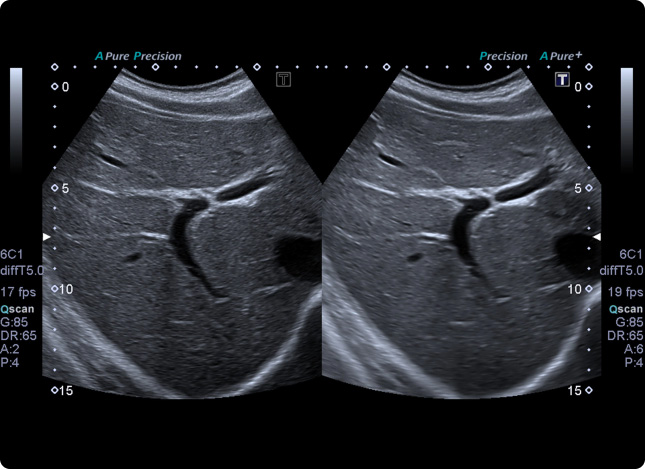

Bei der komplett schmerzfreien Sonografie werden Ultraschallwellen in den Körper gesendet, vom Gewebe unterschiedlich reflektiert und in ein Video-Bild umgewandelt. Somit ist es möglich, Größe, Lage und Struktur Ihrer Organe zu beurteilen bzw. Veränderungen festzustellen.

Mittels eines Gels wird der Arzt zunächst den Kontakt zwischen Ihrer Haut und der Ultraschallsonde herstellen. Die Untersuchung selbst dauert nur wenige Minuten, und auf Wunsch können Sie parallel auf dem Bildschirm die Sonografie mitverfolgen.